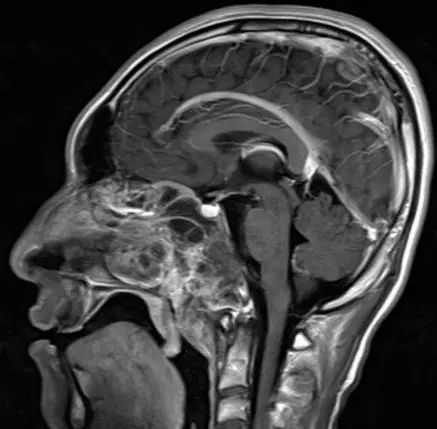

术前MRI显示肿瘤累及斜坡,鼻窦,咽后壁